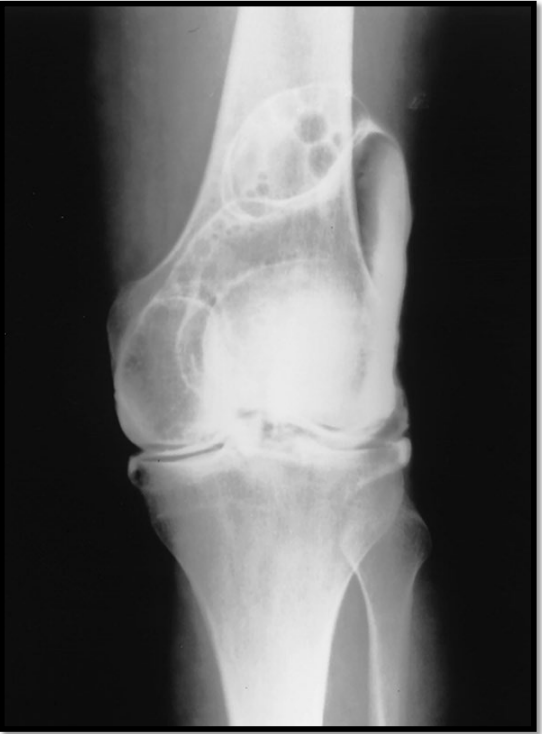

What is wrong in this arthrogram

A

• tear in meniscus allowing contrast to leak out